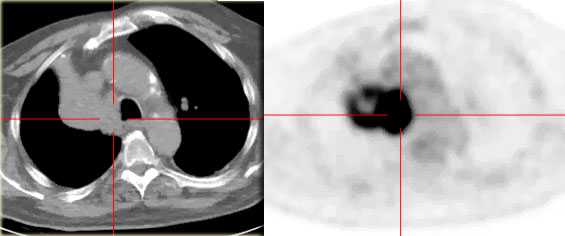

КТ органов грудной клетки. Ателектаз верхней доли правого легкого, обусловленный злокачественной опухолью правого верхнедолевого бронха

На ПЭТ/КТ визуализируется опухоль легкого с обструкцией правого верхнедолевого бронха, как следствие ателектаз верхний доли правого легкого.

На КТ снимках синей стрелкой указан долевой ателектаз, а красной стрелкой опухоль, которая обтурирует левый верхний долевой бронх (центральный рак легкого.